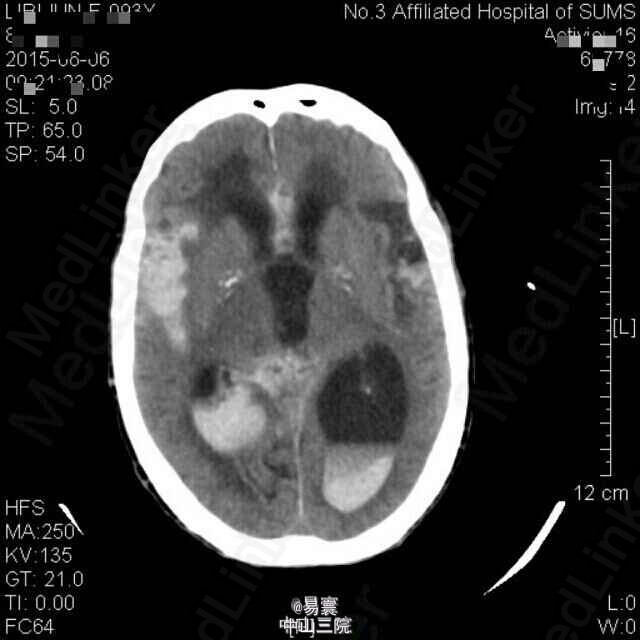

入院查体:神清,消瘦貌,双肺呼吸音稍粗,可闻及少量湿罗音,心律齐。昏睡至浅昏迷貌,呼叫无睁眼,压眶疼痛刺激可定位,肢体疼痛刺激有回缩,双侧瞳孔等大,直径2mm,未见对光反射,眼球居中,未见眼震,双侧额纹、鼻唇沟对称,平卧位双侧上肢可维持45度平伸3-4秒,双下肢可保持屈膝位,不能抬离床面,双侧腱反射减退,双下肢病理征阳性。脑膜刺激征阴性,余查体不能配合。 辅助检查: 1、入院辅助检查:头颅CT平扫(2015-05-30,我院):1、双侧额顶叶、半卵圆中心、侧脑室旁、放射冠及基底节区多发缺血变性或梗塞灶,建议MRI+DWI进一步检查。2、老年脑。3、双侧颈内动脉硬化。胸部螺旋CT平扫(2015-05-30,我院):1.双肺炎症,双肺下叶轻度支气管扩张,建议治疗后复查。2.左肺下叶外基底段钙化灶。3.双侧少量胸腔积液。4.心包少量积液,主动脉硬化。5.肝右叶小囊肿可能。6.甲状腺双侧叶所见,建议进一步检查。 2、入院5天后突发意识障碍查头颅CT示:1、双侧侧脑室、第三脑室积血,并广泛蛛网膜下腔出血。2、双侧额顶叶、半卵圆中心、侧脑室旁、放射冠及基底节区多发缺血梗塞灶,建议MRI+DWI进一步检查。3、老年脑。4、双侧颈内动脉硬化。

随访:患者现意识仍模糊。 讨论:患者老年女性,脑梗后出现脑出血,出血之前并未予以强力抗血小板药物,仅20mg阿司匹林口服,且院外患者长期服用抗血小板药物,有多发性脑梗病史,考虑与患者年龄大血管硬化有关。出血量较大,积极脱水降颅压,现患者一般情况仍差,分享病例同时想问问同行有什么好的处理方法。